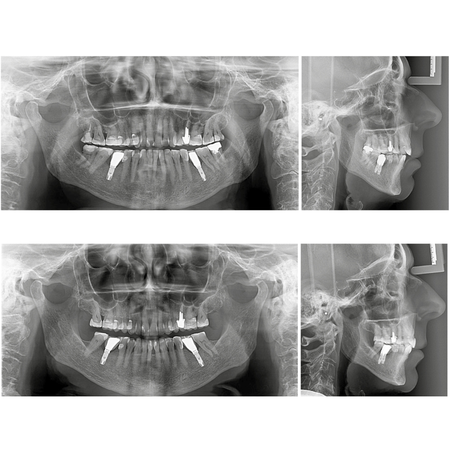

Orthodontic-rehabilitative treatment of Class II malocclusion and anterior open bite in a patient with implants in the lower first molar region: case report treated with aligners

INTRODUCTION: Orthodontic aligners have emerged as an alternative to fixed appliances, particularly for adult patients seeking greater comfort and improved esthetics. OBJECTIVE: This clinical case report describes a 72-yearold female patien...

Class II malocclusion Dental implants Orthodontic treatment Anterior open bite Ceramics veneers Prosthetic treatment